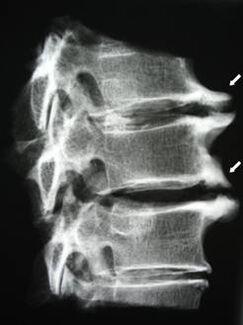

In the initial stages, osteochondrosis is detected using MRI..Subsequently, the pathology can be diagnosed by x-ray.On x-rays of the cervical spine, a decrease in the distance between the vertebrae, pathological changes in the facet joints and osteophytosis are noted.